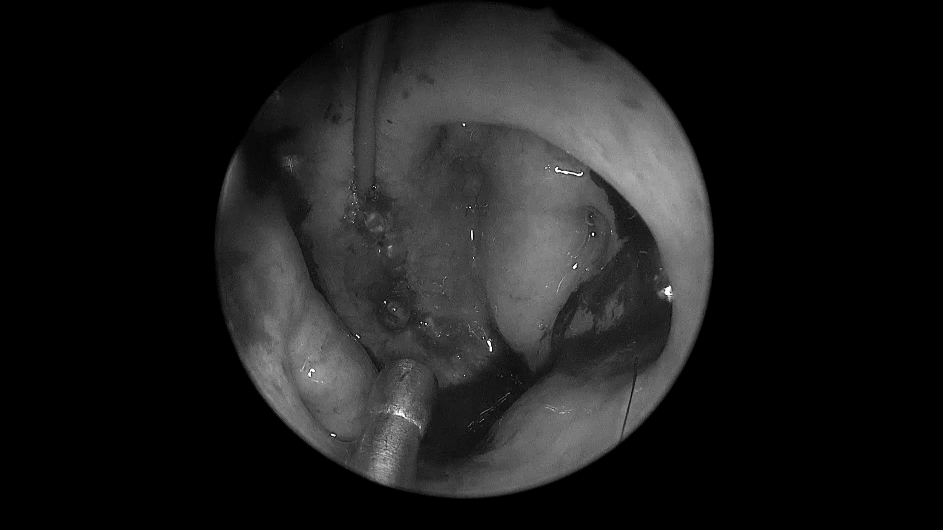

▼单鼻孔进入,粘膜切开

取出部分肿瘤,进行瘤内减压